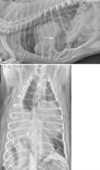

what is the arrow pointing to?

Peritoneopericardial remnant

Which of the following is a radiographic sign specific to a peritoneopericardial diaphragmatic hernia (PPDH) in cats?

B) Dorsal peritoneopericardial mesothelial remnant between the heart and diaphragm

b

which 'sign'/ structure is specific to cats with PPDH?

dorsal peritoneopericardial mesothelial remnant